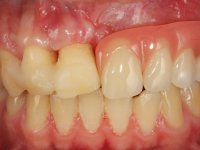

Male patient, 22 years old, non-smoker, appear in our dental office 6 months after a car accident where he lost teeth 21, 22, 23 and 24. Teeth 12 and 11 present mobility grade III, thus with a prognosis of extraction. The gengiva architecture of the edentulous area presents a recession and a flat surface.